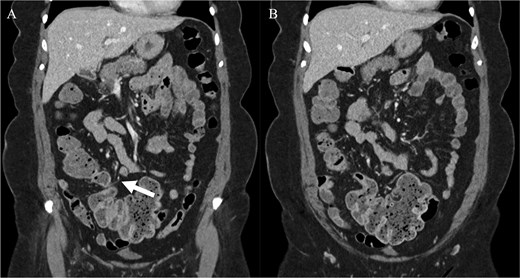

We report the case of a 71-year-old female who presented with a long history of abdominal pain and cramps since childhood. These symptoms had increased and been associated with bloating since a recent bout of uncomplicated sigmoid diverticulitis which was managed conservatively. She had recently had a colonoscopy which had failed to identify any abnormality. A computed tomography (CT) scan showed a distended caecum and suggested a degree of stenosis in the proximal ascending colon (Fig. 1). Her surgical history included an upper midline laparotomy extending to the umbilicus for an open cholecystectomy and an abdominoplasty.

Computed tomography imaging of the patient pre-operatively. (A) The structure suspected to be the band partially obstructing the caecum is indicated by the arrow. (B) The distension of the caecum prior to the obstructing band is demonstrated.